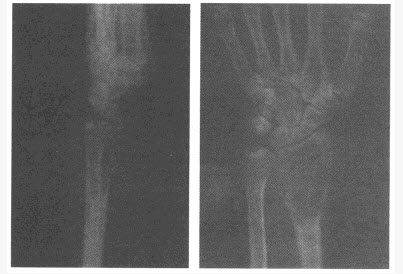

女,40岁,右桡骨远端疼痛5月余,局部压痛。结合右腕关节正侧位片,最可能的诊断为()

A:成软骨细胞瘤

B:骨巨细胞瘤

C:骨囊肿

D:动脉瘤样骨囊肿

E:骨纤维异常增殖症